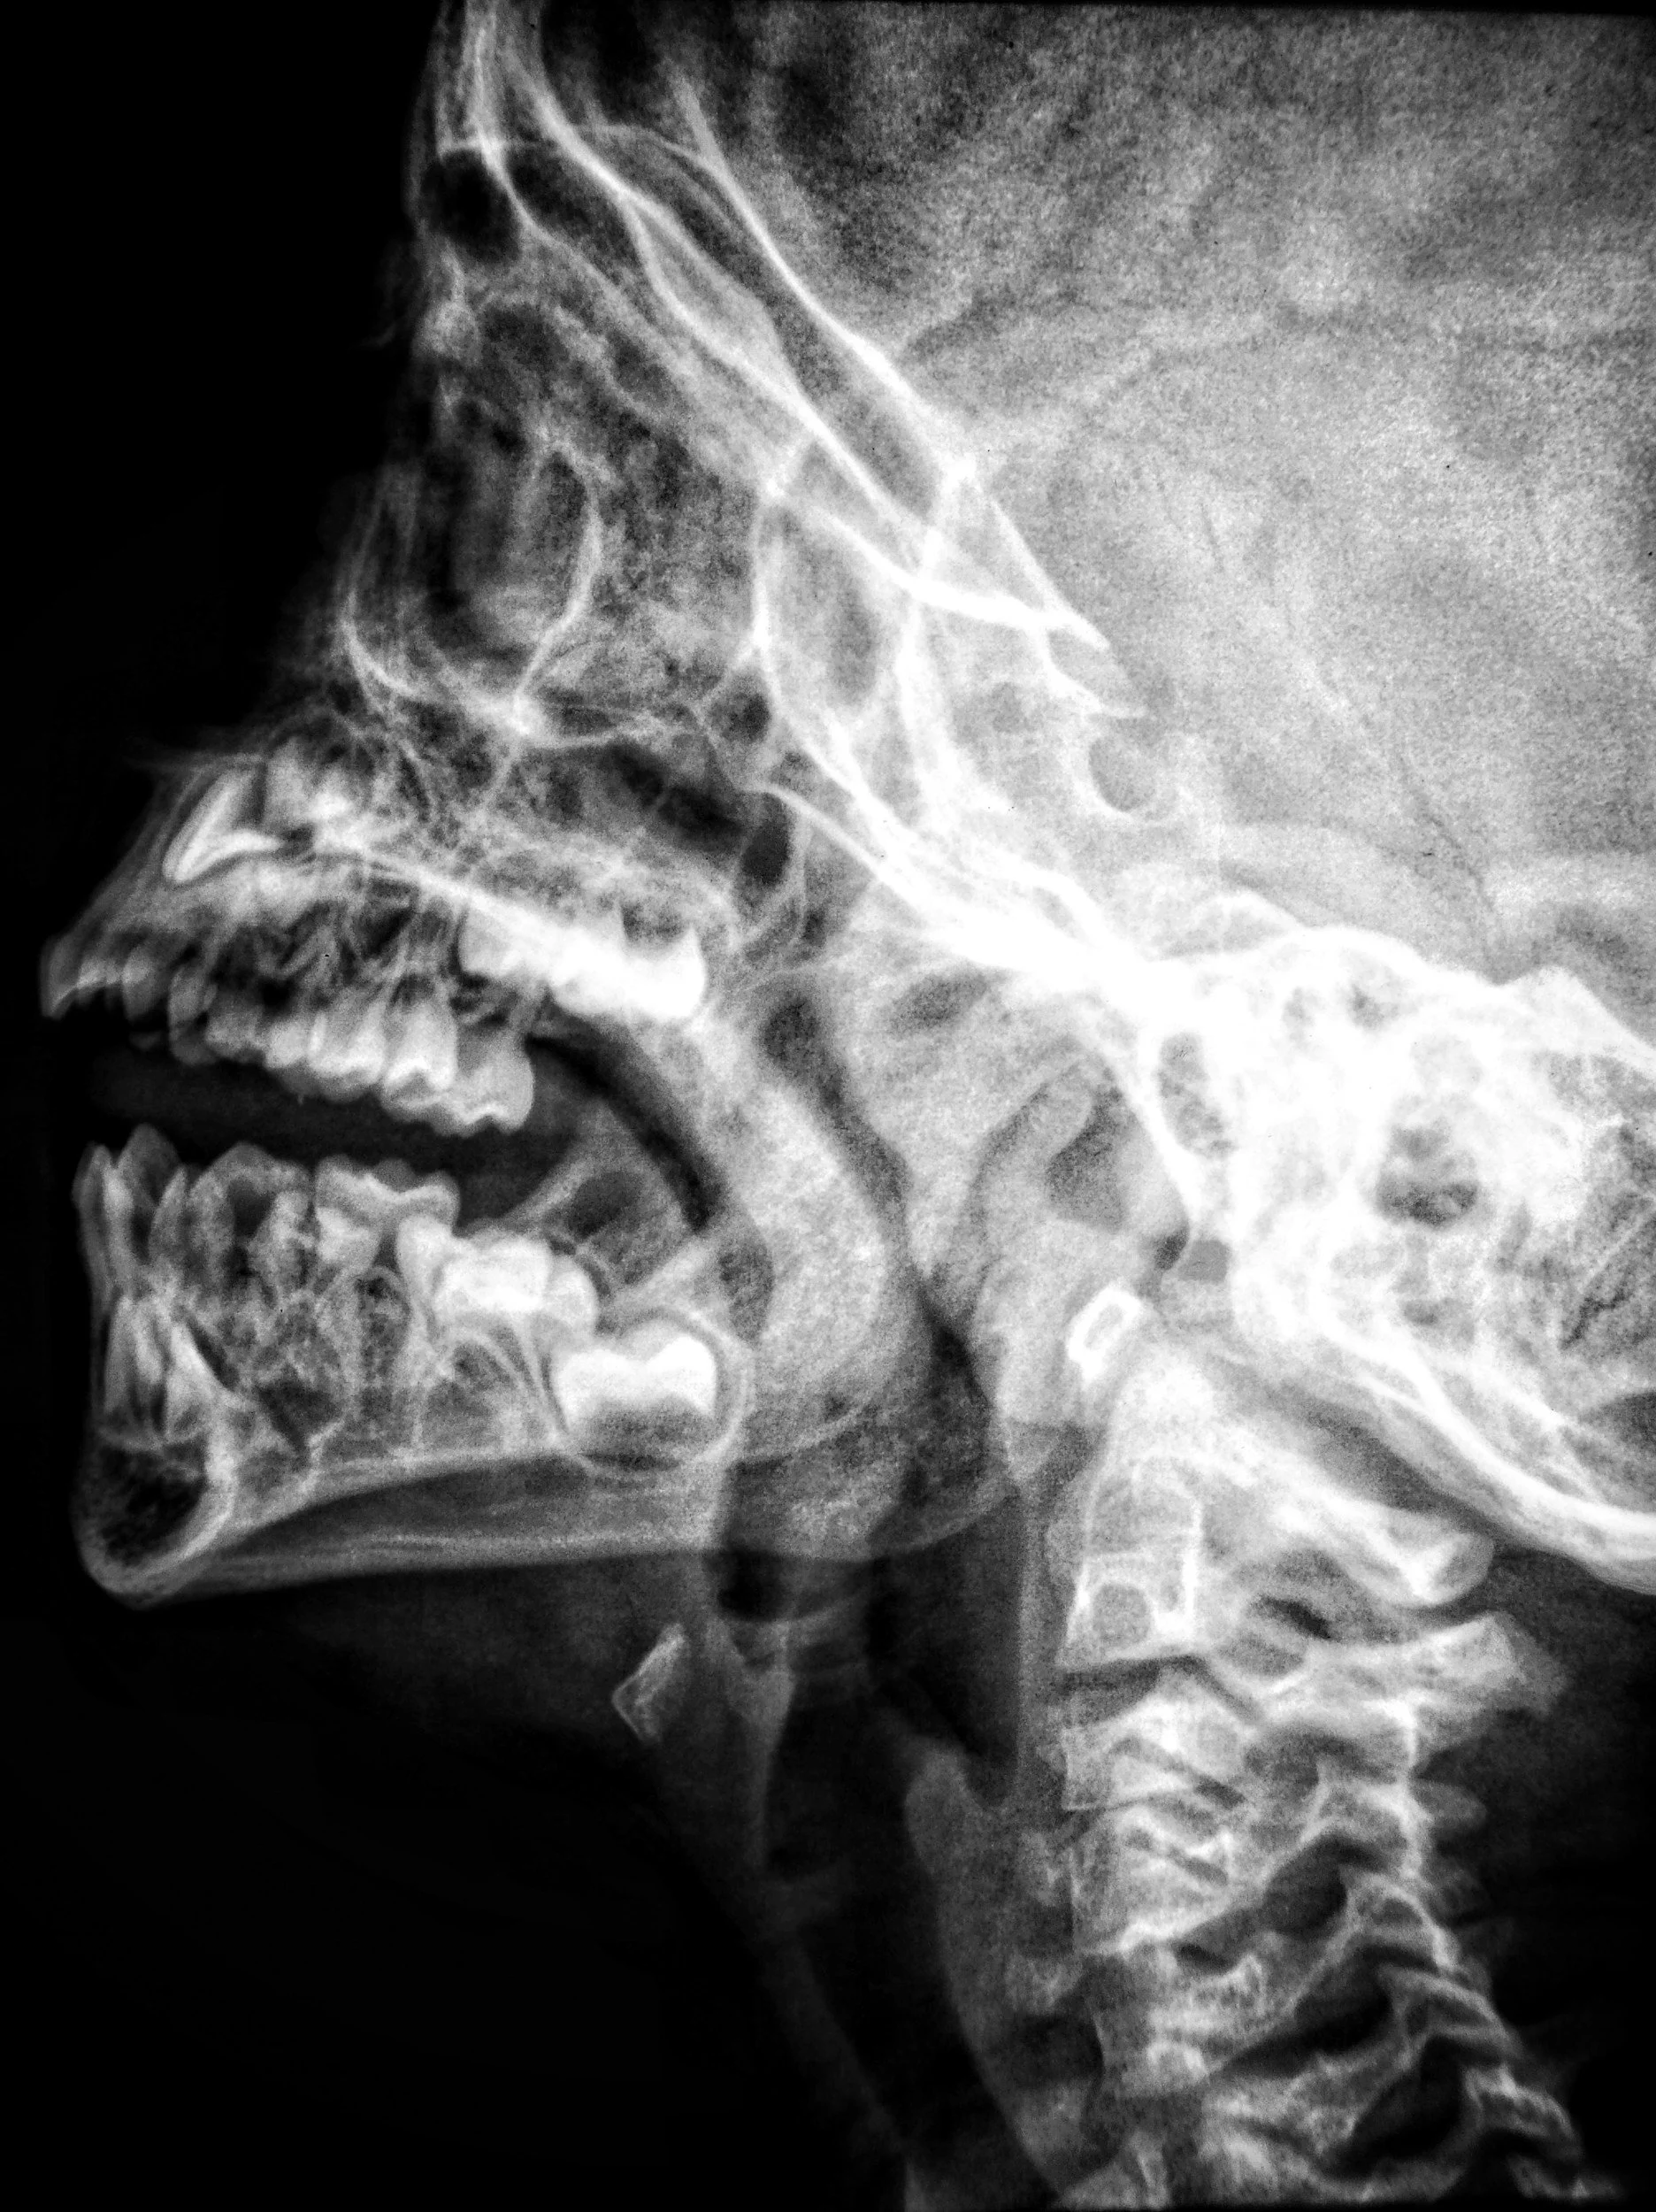

La radiologia diagnostica in odontoiatria permette di individuare in modo accurato problemi nascosti che non sarebbero visibili a occhio nudo. Grazie a strumenti digitali avanzati, come panoramiche e TAC 3D, è possibile ottenere immagini nitide e immediate riducendo al minimo le radiazioni. Questo consente di pianificare terapie più mirate e sicure, garantendo diagnosi precise e personalizzate.

La radiologia digitale offre diversi vantaggi: immagini ad alta definizione in pochi secondi, una dose di radiazioni ridotta rispetto alle tecniche tradizionali e la possibilità di archiviare e condividere i dati in modo semplice. Ciò significa diagnosi più rapide, controlli più sicuri e una migliore comunicazione tra medico e paziente.